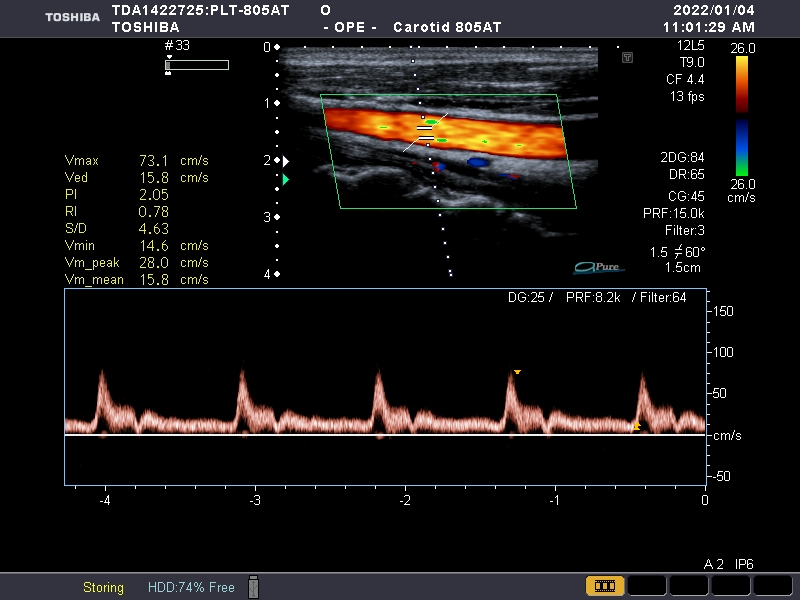

Toshiba PLT-805AT Ref Vascular Linear

Toshiba PLT-805AT

Intended use

Small Parts/Vascular

Frequency Range

6-12 MHz

Toshiba PLT-805AT Vascular Linear

Frequency Range: 6-12 MHz

| Linear | Breast, Carotid, Small parts, Superficial Tissue, Thyroid, Vascular |